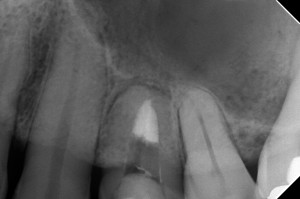

術前。正方線

他院にて根管充填後、痛みがひどくなり、再治療の依頼を受けました。

頬側根にGPが残ってますね

術後。正方線

シーラーパフが・・・根尖が大きく開いてました

1根尖性の2根管ですね